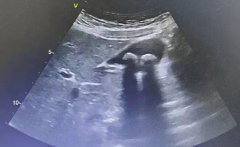

超声科